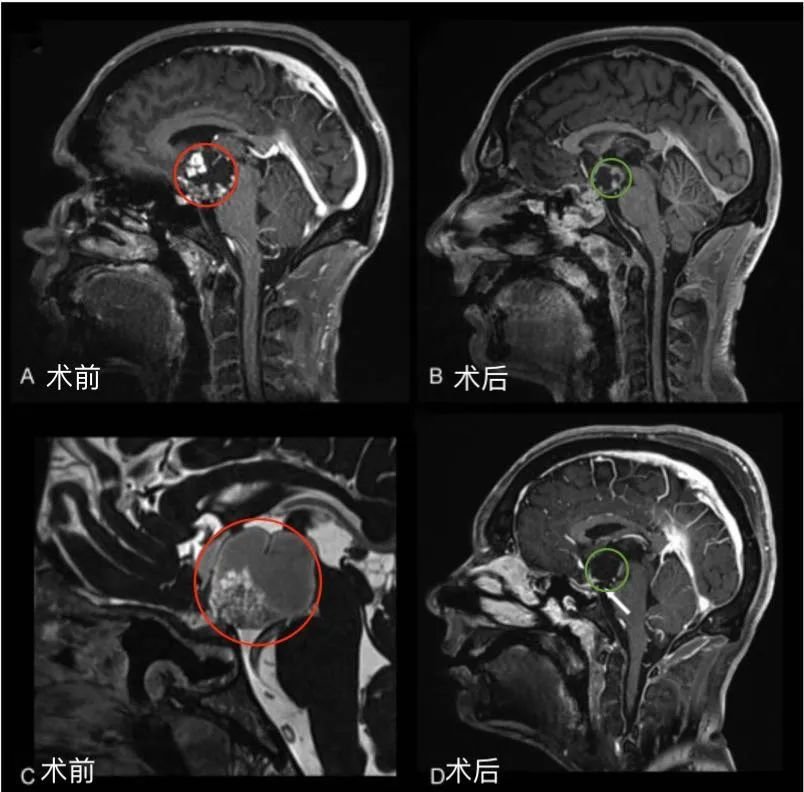

李奶奶的術(shù)前術(shù)后MRI對(duì)比,紅色為術(shù)前腫瘤位置,綠色為術(shù)后切除效果

術(shù)后情況:術(shù)后一天ICU查房李奶奶和巴教授愉快交流,復(fù)視較術(shù)前好轉(zhuǎn)。術(shù)后四天普通病房查房李奶奶復(fù)視完全好轉(zhuǎn),狀態(tài)很好,可以坐起來(lái)。術(shù)后兩周李奶奶恢復(fù)良好順利出院。

圖1后視交叉性較大顱咽管瘤患者腫瘤術(shù)前(A,C)和術(shù)后(B,D)矢狀位增強(qiáng)MR對(duì)比,顯示腫瘤全切。